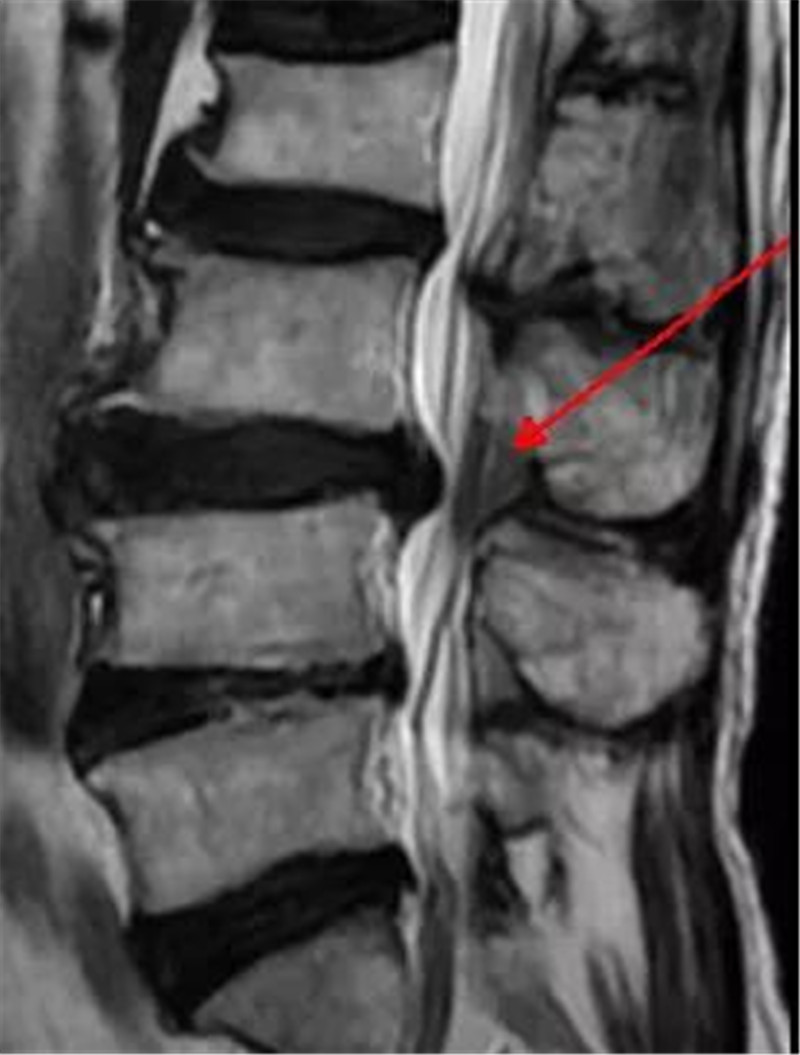

来到三水区人民医院后,医生为他做了系统全面的检查,发现赵伯除了胃出血外,腰椎间盘突出严重,已经压迫到神经,导致他出现腿麻腿痛的现象。消化内科住院10天调理好胃之后,在脊柱关节外科潘磊主任的指导下,由薛厚军副主任医师主刀,黄杰彬医师一助顺利为赵伯实施了微创腰椎间盘摘除及神经松解手术,术后两天,赵伯即可下地行走。

椎间盘巨大突出,右侧神经受压

本次赵伯的手术就是采用最新引进的德国Delta大通道脊柱内镜系统,手术非常顺利,术后病人感觉也很好。“Delta内镜系统是在孔镜基础上发展起来的,它弥补了孔镜的一些不足,对于一些特殊的颈椎间盘突出、腰椎间盘突出、腰椎管狭窄症患者操作更简便,同时又具有创伤小、出血少、术后功能恢复快、感染率低等优点,对老年性椎管狭窄等患者优势更明显。”黄杰彬医师说。